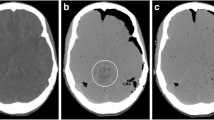

Radiodensity in Hounsfield units (HU) of the VH and CSF were measured by two researchers. Circular regions of interest (ROI) automatically calculated the mean using IMPAX (software version 6.5.3.1005, Agfa Healthcare). The radiodensity of the CSF was determined by the mean of 4 measurements with a maximum fitting ROI positioned in the anterior and posterior horns of the left and right ventricles, excluding the choroid plexus or visible beam hardening artifacts of plexus calcifications. The radiodensity of the VH was determined by the mean value of the left and right VH, excluding the lenses (Fig. 1).